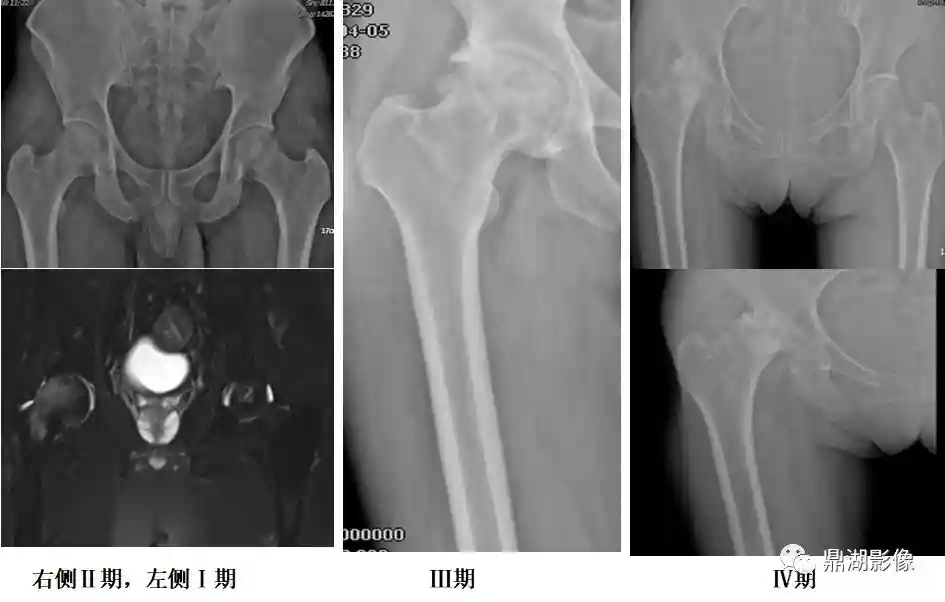

股骨头坏死分期:

0期:所有检查都正常

Ⅰ期:X线、CT正常但MR异常,MR表现出股骨头内线状或带状异常信号,T1WI呈低信号,T2WI呈双线征

Ⅱ期:X线可见异常,硬化、骨小梁缺失,局部有囊变

Ⅲ期:股骨头关节面扁平

Ⅳ期:骨关节炎、关节间隙变窄,髋臼改变、关节破坏等